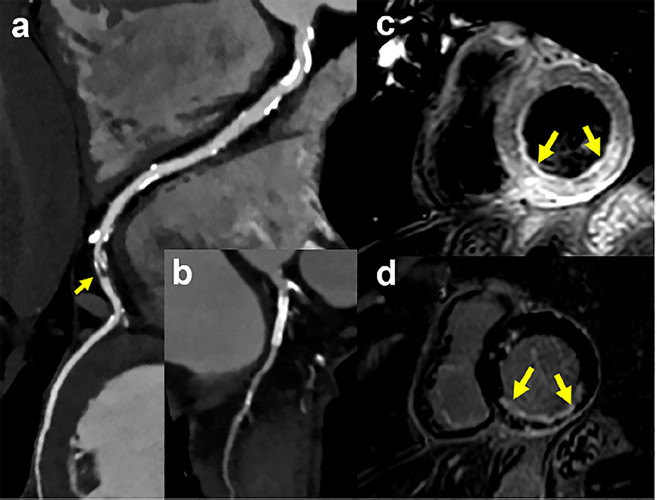

Se efectuó un ecocardiograma transtorácico, que indicó función global ventricular izquierda preservada (fracción de eyección ventricular izquierda 58%) con hipocinesia inferior e inferolateral. Se solicitó una TC (Escáner IQon Spectral, Philips Healthcare, Países Bajos) para descartar un origen embólico (Figura 1). Las imágenes realzadas mediante contraste identificaron la presencia de tromboembolismo pulmonar (Figura 1, panel a, flecha) y un marcado defecto de perfusión de la pared ventricular izquierda basal inferior (Figura 1, panel b, flechas). Se detectó un stent permeable en la arteria circunfleja izquierda, a la vez que se identificó una lesión irregular grave en la arteria coronaria derecha (grande y dominante) distal (Figura 2). Es de destacar que utilizando imágenes de DE, el score de calcio coronario sin contraste (colimación 32 × 0,625, espesor 2,5 mm, 120 kV, 80 mAs, velocidad de rotación 0,33 segundos, gatillado al 75% del intervalo RR), permitió detectar tanto el tromboembolismo pulmonar

La resonancia magnética cardíaca confirmó los hallazgos (Figura 2) mostrando edema miocárdico transmural utilizando imágenes ponderadas en T2, y un infarto subendocárdico inferior.